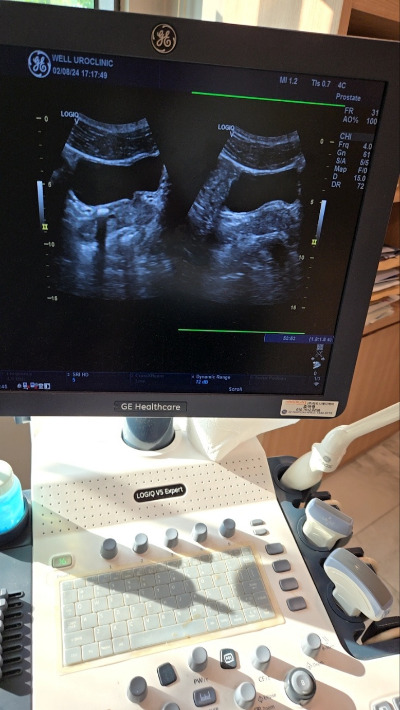

비뇨기과, 심장내과 비뇨기과는 콩팥이 많이 안 좋아져서 신장하고 방광 쪽에 1.5cm 이상 크기에 결석, 조금만 한 결석들을 제거하기 위해 결국은 체외충격파 쇄석술을 꼭 해야 한다 하셨다.

img.jpg